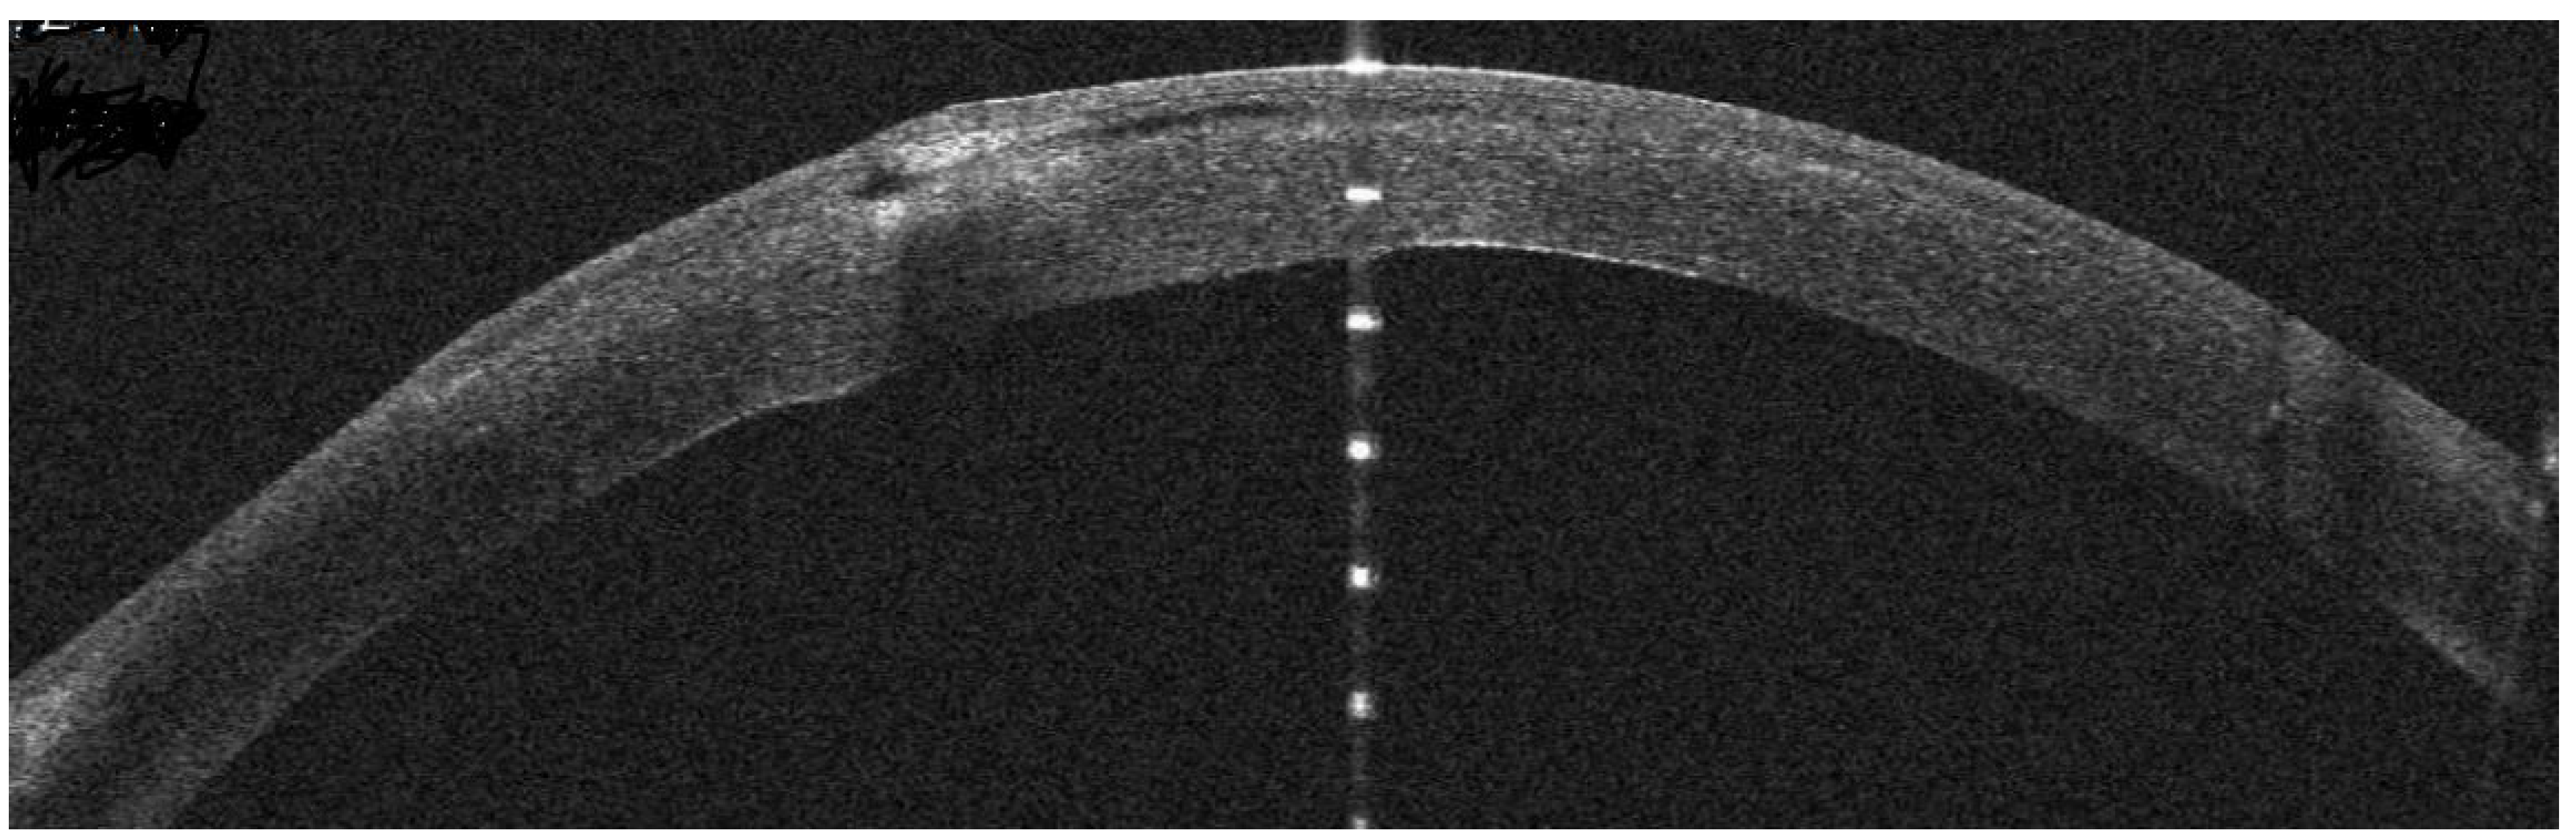

AS-OCT Features

Infectious Keratitis Post-Femtosecond LASIK

Patient #1